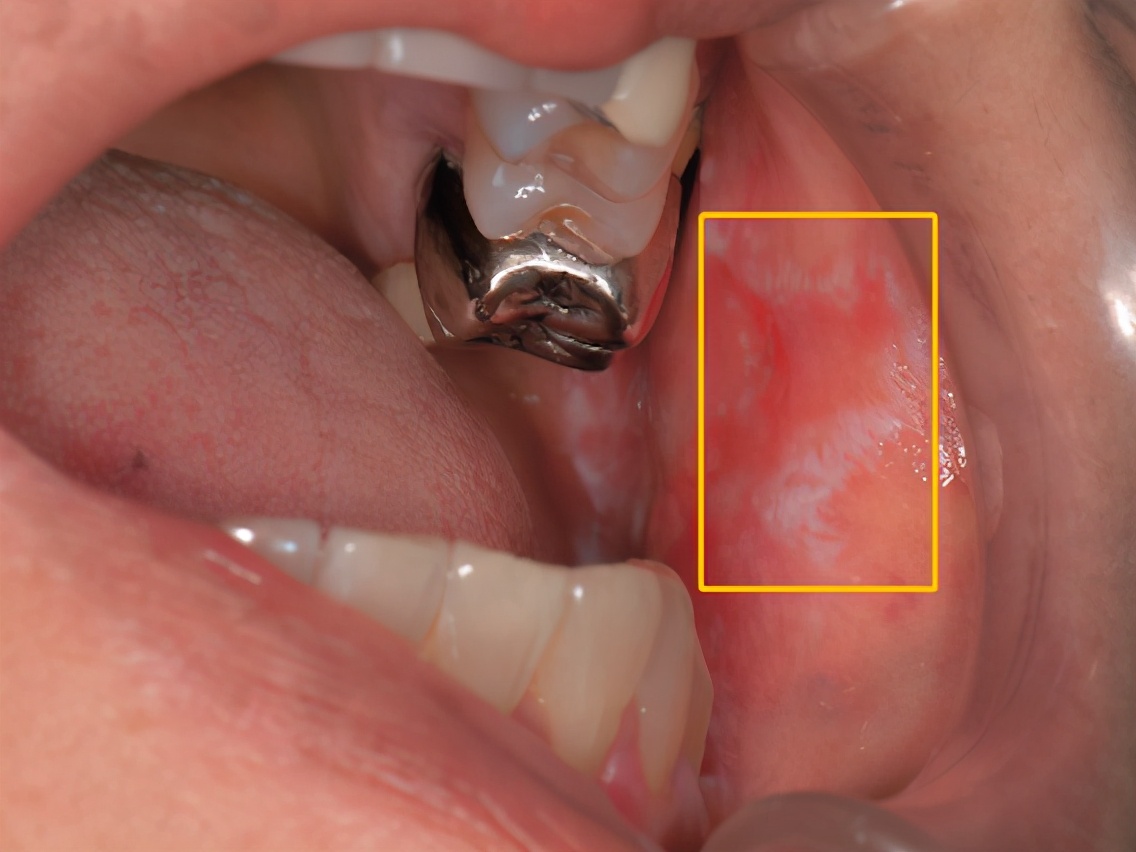

张女士,53岁,某天感觉在口腔内侧腮部有粗糙感,张嘴对着镜子一看,隐约在腮部黏膜上看到一些白色类似网状格子的条纹,约有硬币大小,左右两边都有。张女士以为是脏东西,但是怎么都擦不掉,除了粗糙感之外,没有任何不适,张女士虽然疑惑,但是渐渐地也没太在意。

过了一段时间后,张女士感觉自己吃刺激性食物时口腔会有刺痛感,对着镜子一看,发现白色网状条纹范围增大了,而且中间还夹杂一些红色糜烂,害怕是口腔癌,就立即上医院检查了。

经过检查,医生告诉张女士,这可能是口腔扁平苔癣,确诊需要活检。一周后,活检结果出来了,确实是口腔扁平苔藓。

口腔扁平苔藓是一种常见的慢性炎症性口腔黏膜皮肤疾病,它长在口腔黏膜上的形状就跟苔藓差不多,所以就叫口腔扁平苔藓,并不是我们日常生活中苔藓的意思。